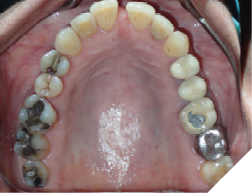

The majority of the orthodontic practices offer a period of “supervised retention” to their patients and communicates the customized retention recommendation with the patient’s general dentists. It is extremely important to work as a team to achieve long term clinical success in maintaining a functional bite and aesthetic smile. The general dentists continue to see their patients on a regular basis and have an opportunity to assess the orthodontic retainers and the bite after the supervised retention period is completed by the orthodontists. With great care, orthodontic retainers would serve for a long time (Fig. 1) without any major issues. However, in some cases, the failure to notice the clinical problems early on results in functional issues that would require a comprehensive orthodontic treatment to correct it (Fig. 2).

Fig. 1A

Fig. 1B

Fig. 1C